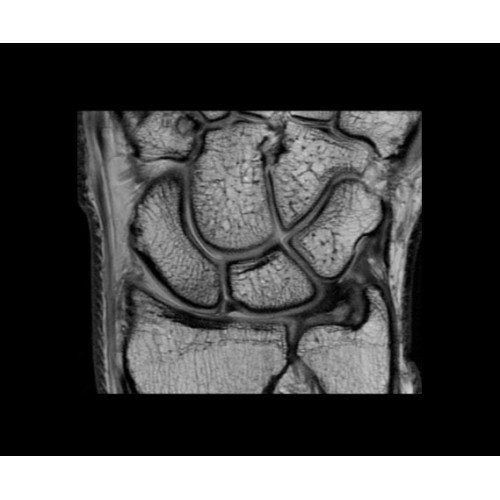

SIGNA PET/MR 3.0T — это гибридная система, в которой совмещаются две принципиально разные технологии — магнитно-резонансную томографию (МРТ) и позитронно-эмиссионную томографию (ПЭТ). Система отличающийся высокой чувствительностью и эффективностью и предназначена для диагностики в области онкологии, неврологии, кардио-васкулярных исследований, исследований воспалительных процессов.

Компания GE Healthcare представляет революционную, полностью интегрированную систему SIGNA PET/MR1, в которой сочетаются времяпролетная технология (TOF) и возможности напряженности магнитного поля 3.0 Тл. Мы поможем вам поднять исследования на более высокий уровень. SIGNA PET/MR позволяет достичь впечатляющей точности и скорости исследований, а благодаря новейшей технологии реконструкции Q.Clear2 качество изображений улучшается в два раза. Кроме того, в систему включен полный набор клинических приложений и гибких катушек для проведения любых видов исследования, открывая для вас возможности визуализации, о которых вы даже не догадывались.

Кроме того, в результате использования технологии TOF и инновационной технологии реконструкции Q.Clear вы сможете добиться прекрасного соотношения сигнал/шум. А благодаря технологии нулевого времени эхо (ZTE) визуализировать костную структуру без ионизирующего излучения. Все эти разработки для улучшения качества сканирования и точности анализа помогут вам использовать весь потенциал ПЭТ/МРТ.